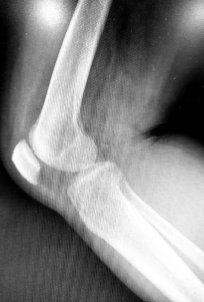

무릎은 하반신과 상반신을 연결하는 관절로서, 대퇴골, 종아리뼈, 장골로 이루어져 있습니다. 몸의 무게 중심을 지탱하고, 다양한 움직임을 수행하는 중요한 관절 중 하나입니다. 하지만, 무릎은 무거운 무게를 지탱하며 일상생활에서 노출되는 부위이기 때문에 다양한 질환과 부상의 위험이 있습니다. 적극적인 관리와 근력 강화를 통해 무릎 건강을 유지하는 것이 중요합니다.

무릎 연골 정보

무릎 연골 손상 원인

무릎 연골 손상의 원인은 크게 두 가지로 나눌 수 있습니다. 첫 번째는 외상성 원인입니다. 이는 무릎에 강한 충격이 가해지거나, 무릎을 굽힌 상태에서 회전하는 등의 동작으로 인해 발생하는 경우입니다. 스포츠 활동 중 넘어지거나 부딪히거나, 교통사고를 당하거나, 높은 곳에서 뛰어내리는 등의 상황에서 무릎 연골 손상이 일어날 수 있습니다.

두 번째는 퇴행성 원인입니다. 이는 나이가 들면서 무릎 연골이 자연스럽게 마모되고 약해지는 경우입니다. 비만이나 관절염과 같은 질환, 반복적인 운동이나 과도한 부하 등으로 인해 무릎 연골이 닳아서 손상될 수 있습니다.